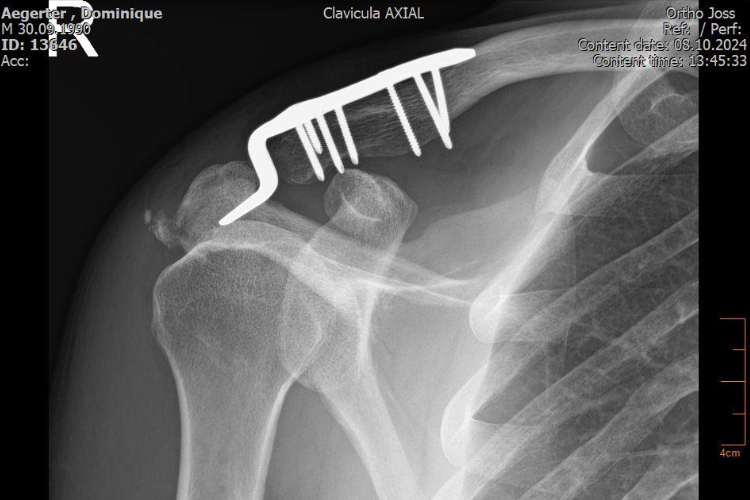

Dominique Aegerter continue de surveiller de près son état de santé après son accident d’entraînement en VTT fin août, au cours duquel il a subi plusieurs fractures – quatre côtes du côté droit, une clavicule, ainsi que des fissures à l’omoplate et à l’acromion. Pour évaluer sa guérison, il a récemment fait passer des scans en Suisse afin de documenter l’évolution de sa récupération.